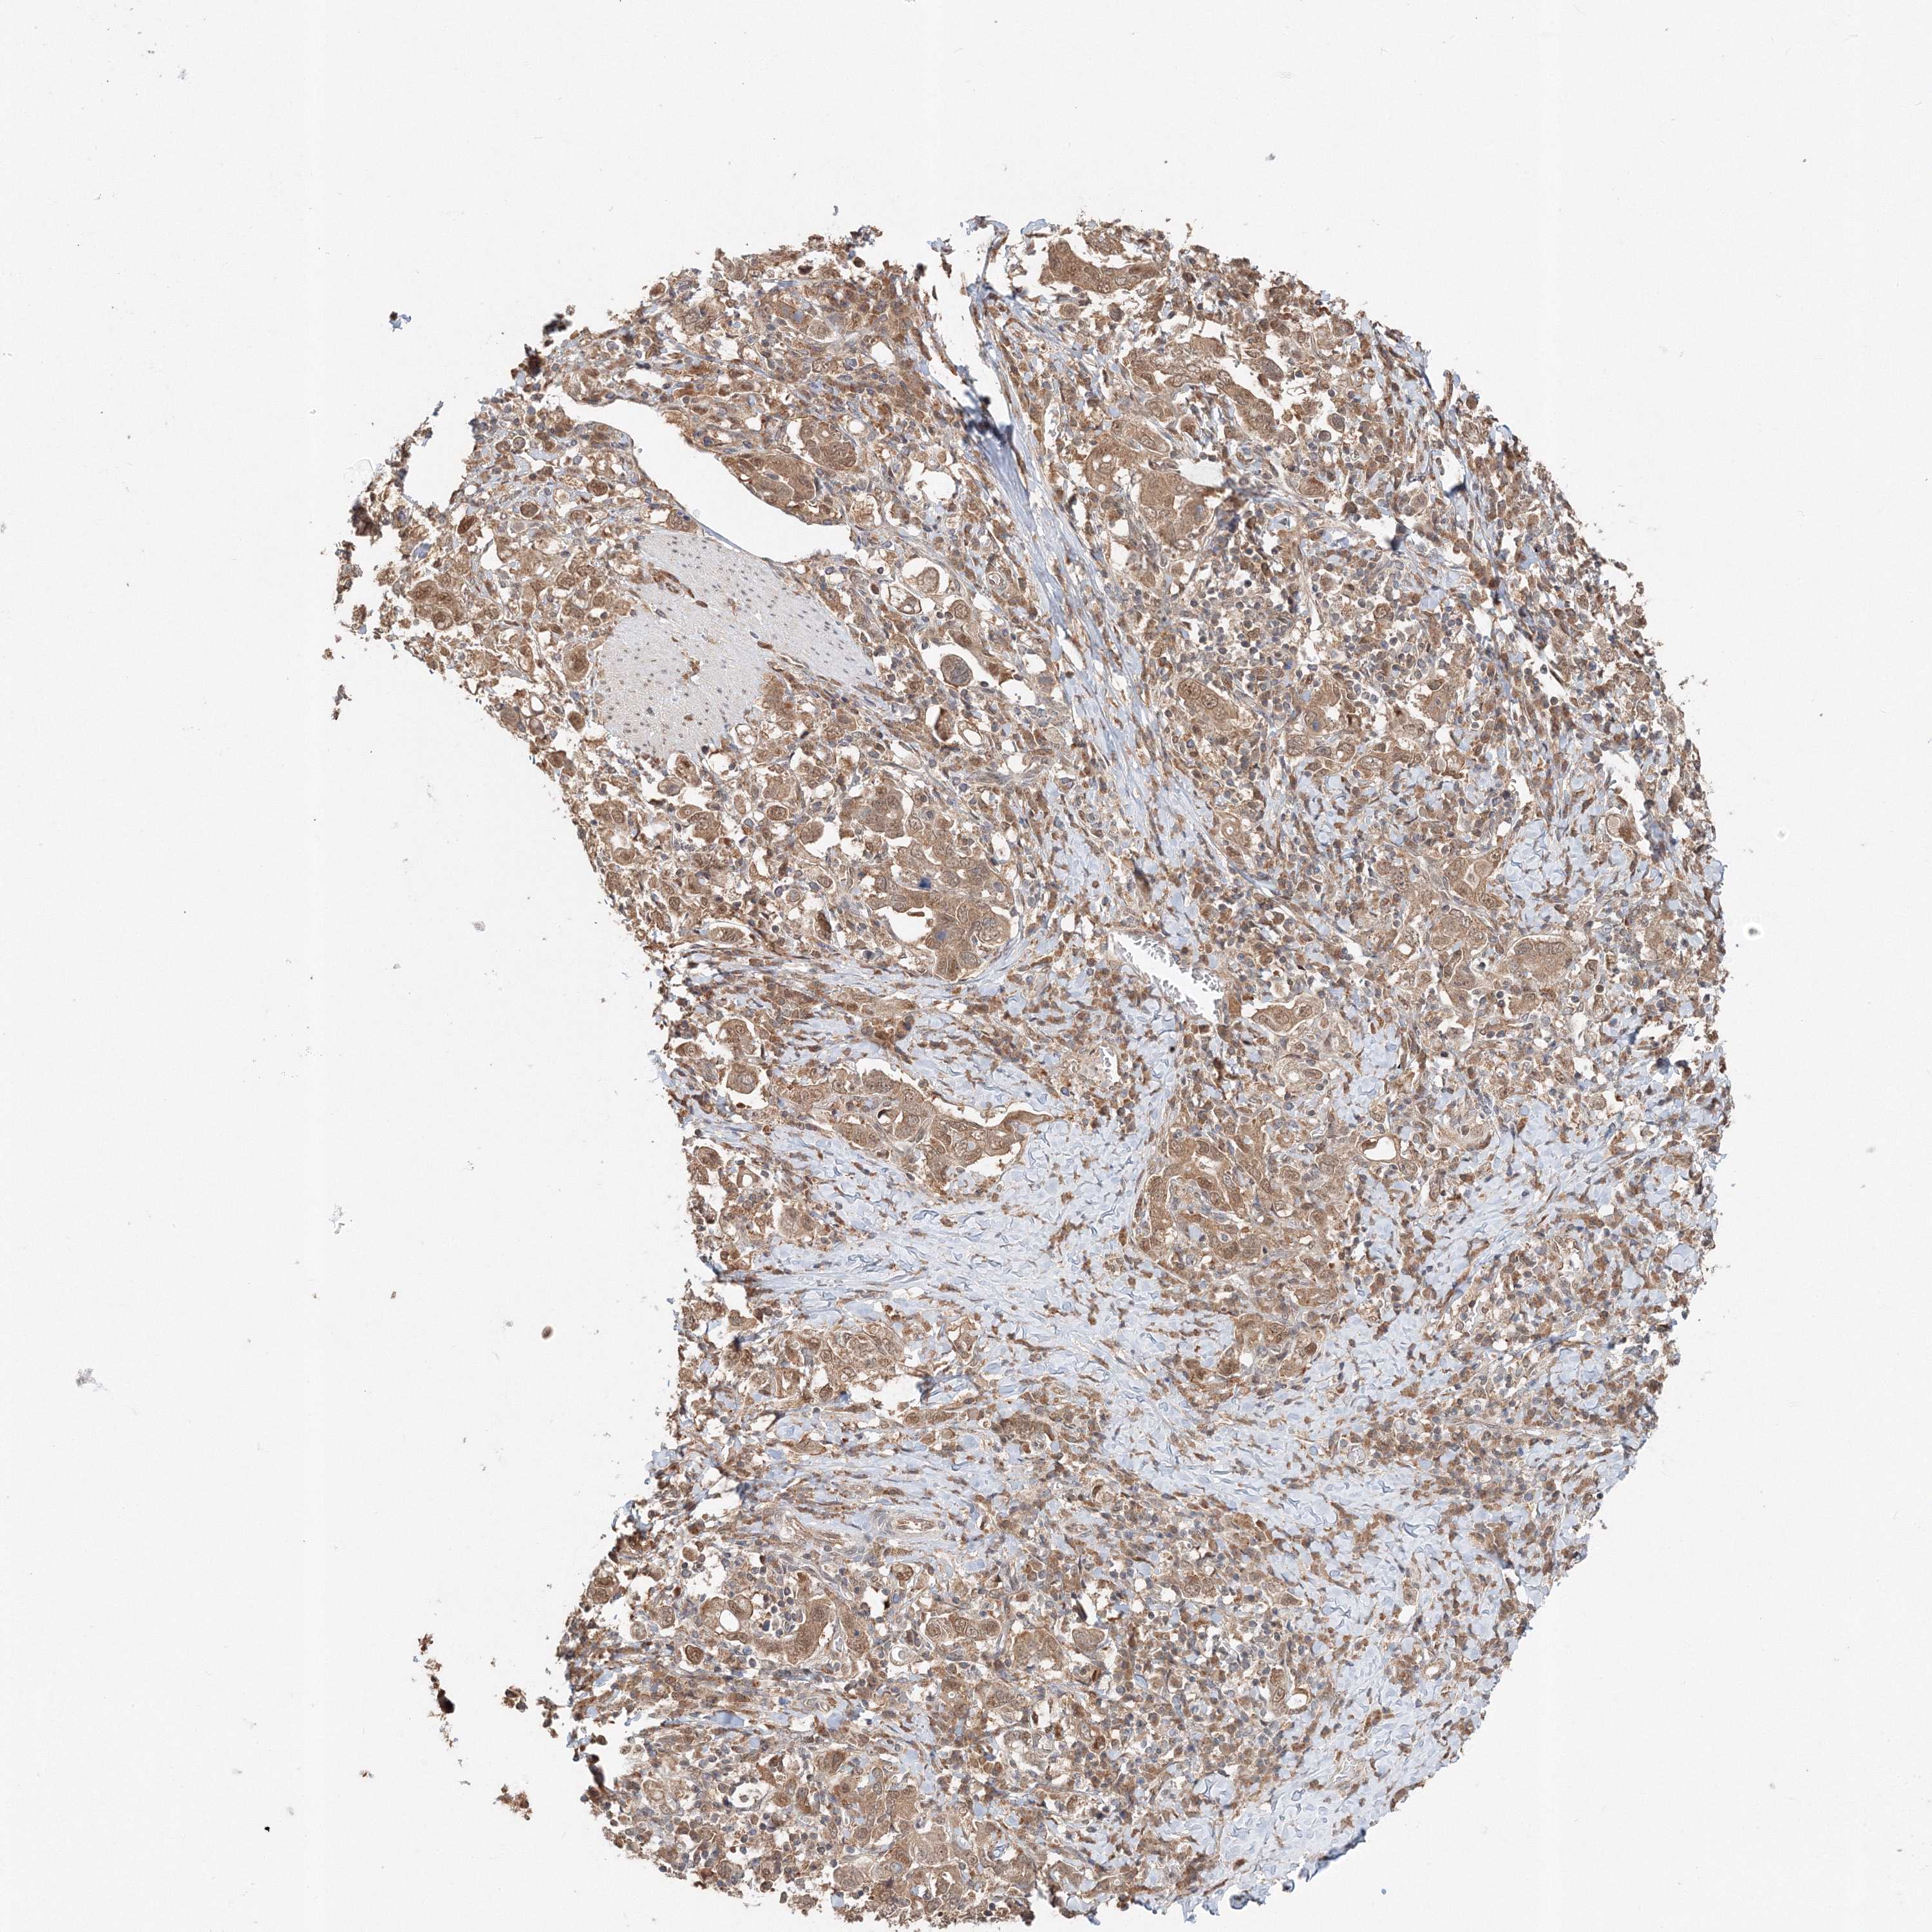

STOMACH CANCER - Protein expressioni

A mouse-over function shows sample information and annotation data. Click on an image to view it in a full screen mode. Samples can be filtered based on level of antibody staining by selecting one or several of the following categories: high, medium, low and not detected. The assay and annotation is described here.

Note that samples used for immunohistochemistry by the Human Protein Atlas do not correspond to samples in the TCGA dataset.

Antibody stainingi

Antibody staining in the annotated cell types in the current human tissue is reported as not detected, low, medium, or high, based on conventional immunohistochemistry profiling in selected tissues. This score is based on the combination of the staining intensity and fraction of stained cells.

Each image is clickable and will lead to virtual microscopy that enables deeper exploration of all samples and also displays staining intensity scores, fraction scores and subcellular localization as well as patient and tissue information for each sample.

Antibody HPA036921

Antibody HPA036922

Staining

High

Medium

Low

Not detected

Intensity

Strong

Moderate

Weak

Negative

Quantity

>75%

75%-25%

<25%

None

Location

Nuclear

Cytoplasmic/membranous

Cytoplasmic/membranous,nuclear

Adenocarcinoma, NOS